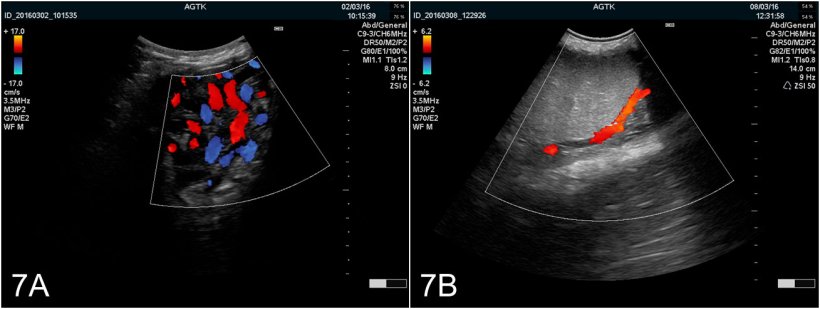

En résumé, l'échographie de l'appareil génital du verrat est une modalité de diagnostic viable qui peut fournir des informations précieuses sur la fonction et la santé du tissu. Même si l'utilisation pratique est actuellement limitée, l'auteur est fermement convaincu que l'utilisation de cette méthode (et d'autres comme le Doppler couleur [Figure 7A et B]) obtiendra une plus grande utilisation chez les vétérinaires porcins comme un outil pour prédire le rendement potentiel des éjaculats et pour diagnostiquer avec précision les problèmes de subfertilité et d'infertilité associée à des tissus malades.

Figure 7: Images du testicule obtenues par échographie Doppler couleur A) Vaisseaux du cordon spermatique B) Artère testiculaire